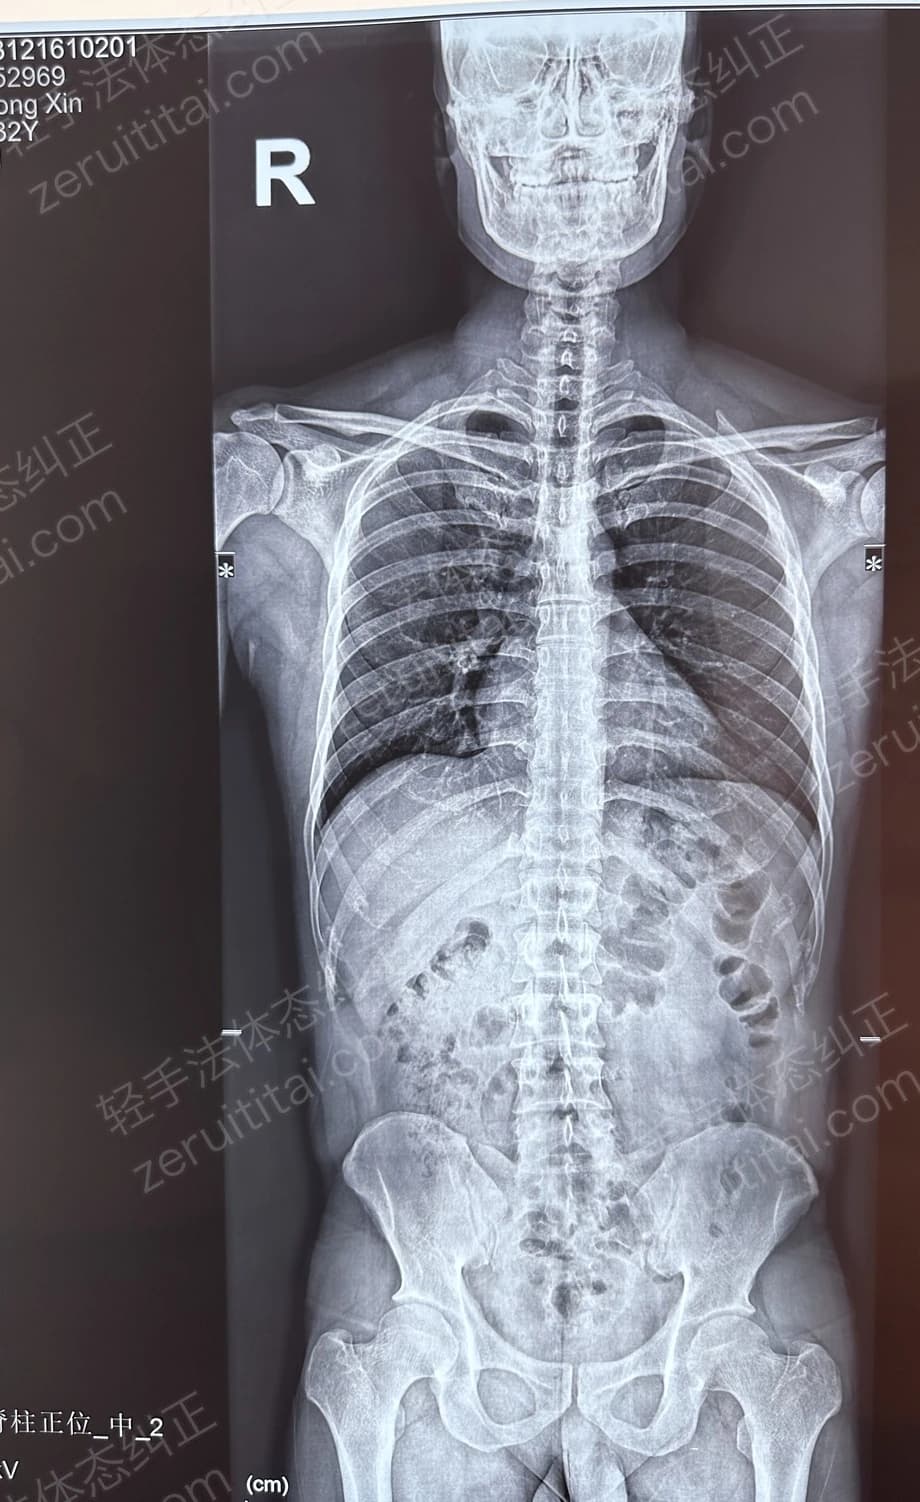

2023.12.16

第 5 次记录